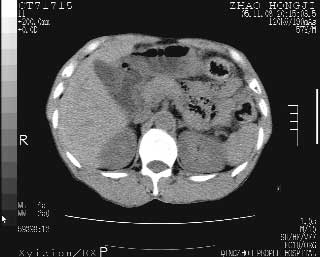

临床资料:男性,57岁,上腹部疼痛并5天,突然加重并延及全腹伴恶心5小时入院。胰淀粉酶化验在正常范围。检查:腹肌紧张,全腹压痛、反跳痛,尤以右上腹部为著。肠鸣音减低。血常规:wbc14.6x10/9, n:11.3x10/9 ,血压:135/90mmhg. 胸部透视:腹部肠腔轻度张气,未见其它异常改变。

肝右前缘少量积气,其他未见明显异常.考虑上消化道穿孔.

小网膜囊积气液,胃壁僵硬。考虑胃穿孔。

小膜网膜积液,肝缘气腹征,上消化道穿孔。

肝缘见少许气体,胰尾部见少许气体包饶(蓝色圈),12指肠上部或球部邻近胆囊周边也可见少许气体影(黄色圈),并忖托出胆囊壁,12指肠远段肠道内未见明显气体(白色箭)。

肝脏前缘见少量积气、胰尾部见少许气体包饶,肾前筋膜未见增厚,临床淀粉酶不高,意见:上消化道穿孔。

入院3小时后行剖腹探查术,见腹腔内大量脓性混浊液约1000ml,十二指肠球部溃疡穿孔,溃疡面约2.5x2cm,穿孔直径约0.6cm。胃内容物外益,周围组织炎性水肿明显。行十二指肠穿孔修补术。术后诊断:

1、十二指肠溃疡穿孔

2、弥漫性腹膜炎

对于少量的腹腔游离气体,ct检查较普通透视有绝对的优势,它不仅可以看到肝脏前上缘的气体,而且还能够看到小网膜区的游离气体。从而可以肯定诊断。各位分析战友的很好,感谢大家的参入!